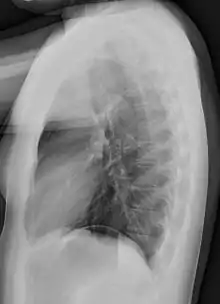

Different views (also known as projections) of the chest can be obtained by changing the relative orientation of the body and the direction of the x-ray beam. The most common views are posteroanterior, anteroposterior, and lateral. In a posteroanterior (PA) view, the x-ray source is positioned so that the x-ray beam enters through the posterior (back) aspect of the chest and exits out of the anterior (front) aspect, where the beam is detected. To obtain this view, the patient stands facing a flat surface behind which is an x-ray detector. A radiation source is positioned behind the patient at a standard distance (most often 6 feet, 1,8m), and the x-ray beam is fired toward the patient.

Lateral views of the chest are obtained in a similar fashion as the posteroanterior views, except in the lateral view, the patient stands with both arms raised and the left side of the chest pressed against a flat surface.